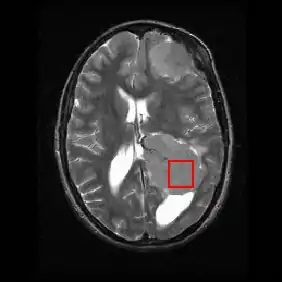

Shown below is an MRI brain scan (in the axial plane, that is slicing from front-to-back and side-to-side through the head) showing a brain tumor (meningioma) at the bottom right. The red box shows the volume of interest from which chemical information was obtained by MRS (a cube with 2 cm sides which produces a square when intersecting the 5 mm thick slice of the MRI scan).

Each biochemical, or metabolite, has a different peak in the spectrum which appears at a known frequency. The peaks corresponding to the amino acid alanine, are highlighted in red (at 1.4 ppm). This is an example of the kind of biochemical information which can help doctors to make their diagnosis. Other metabolites of note are choline (3.2 ppm) and creatine (3.0 ppm).